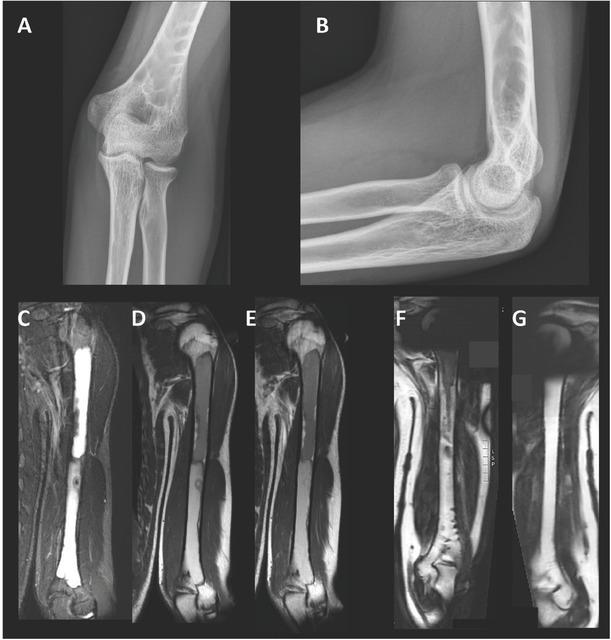

Figure 1

Figure 2